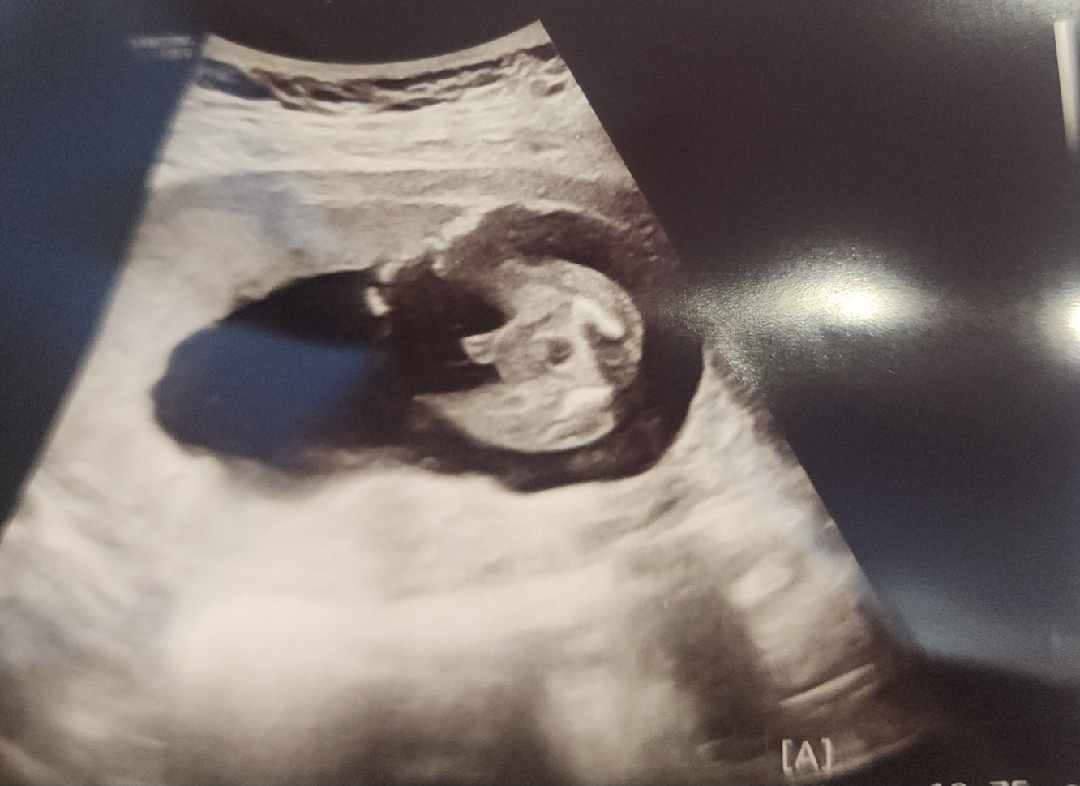

성별을 너무 확실하 알려주네요 ㅋㅋ

첫째 아들과 둘째 딸을 키우고 있답니다 ㅎㅎ 셋째임신인걸 알고 공주를 원했었어요 ㅎㅎ 근데 좀 왔다갔다했어요 ㅎㅎ 둘째딸아이옷 물려받았는데 너무 많아서 이기도 했어여 또 아들이면 자꾸 삐지지 읺으니 정산적 스트레스가 적을거 같고 3돌까지 잘키우면 화장실과 목욕탕을 아빠와 가면 되니 아들도 괜찮겠다 생각했어요ㅋㅋ 몇일전 니프티 결과랑 초음파 보러 내원했는데 기다리는 동안 니프티 결과지를 주셔서 아들인걸 알아버렸죠ㅋㅋ 그러고 초음파를 보니 떡하니 보여주네요ㅋㅋㅋㅋ 첫째가 형아 하거 싶다고 했는데 진짜 형아가 됐아요 ㅎㅎ 둘째도 느나 핳건지 언니할건지 물으니 6~70%로 누나 한다거